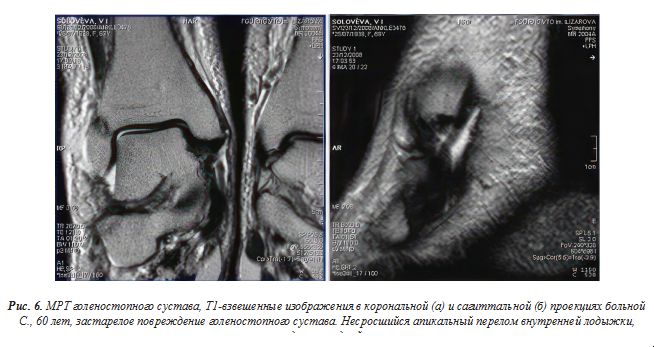

Формирование рубца приводило к гипертрофии связки, значительному неравномерному ее утолщению, дислокации в дистальном направлении, если отрыв произошел на проксимальном уровне. Контуры связок были четкими, волнистыми. В ряде случаев интенсивность сигнала на протяжении связки была неравномерной. Как правило, имел место умеренно выраженный перифокальный отек. В отдаленном периоде идентифицировать разрыв связок у некоторых больных было достаточно сложно из-за рубцовых изменений в зоне повреждения, особенно когда кроме повреждения связок были переломы костей, образующих голеностопный сустав. При разрыве или отрыве других связок, например, дельтовидной (deltoideum) на Т1-взвешенном изображении полученная картина может быть охарактеризована как «симптом пиявки» (рис. 6).